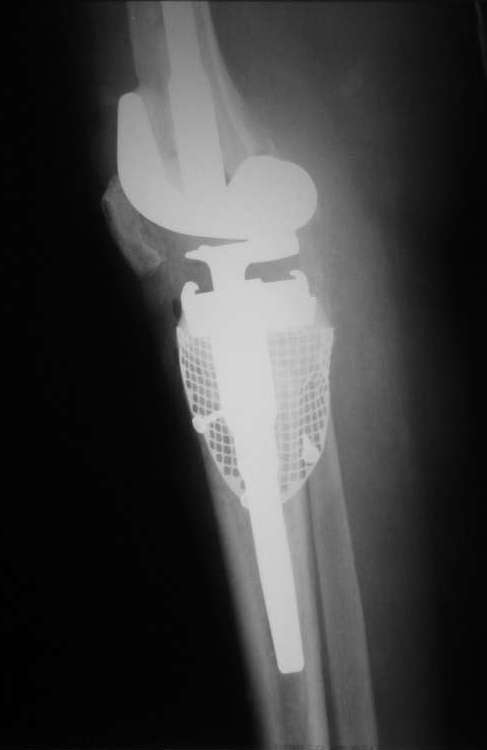

После открытия сустава оказалось, что головка малоберцовой кости возвышается над наружным кортикалом большеберцовой кости на 1 см, а над разрушенным внутренним мыщелком на 3 см (см. фото).

Рассверлили канал большеберцовой кости. В канал поставили стержень. По нему, на наружный кортикал посадили шаблон тибиального компонента (см. фото). Определили размер дефекта внутреннего мыщелка, который надо закрыть сеткой.

На внутренний мышелок установили сетку из нержавеющей стали Ex-Change Stryker (предназначенную для укрепления верхнего края вертлужной впадины) и фиксировали её 4 винтами. Подрезали сетку сверху по шаблону тибиального компонента. После этого рассверлили канал б/б и бедренной костей под протез. Используя систему пульс-лаважа Stryker SurgiLav c насадкой - щеткой для промывания каналов промыли бедренную и большеберцовую кости. Последнее сверло, которым рассверливали проксимальную часть канала б/б кости, оставили на месте. Аллотрансплантат перемололи на костной мельнице, перемешали с 3 гр. ванкомицина и достаточно плотно заполнили им дефект внутреннего мыщелка, утрамбовывая импактором костную стружку в единую массу.

Так как наружный кортикал был на 1.3 см. ниже головки малоберцовой кости, пришлось использовать вставку под большеберцовый компонент 1 см. На цемент c ванкомицином поставили тибиальный компонент с ножкой 11/80 мм.

Бедро по шаблону резецировали (лучше сказать «причесали»). Системой пульс-лаваж с щеткой для отмывания костной поверхности основательно все отмыли и поставили на цемент бедренный компонент c ножкой 11/155 мм.

1) Парез малоберцового нерва. - Через 2 дня после операции чувствительность восстановилась, движений пока нет. Связываем с существенным удлинением ноги при установке протеза.

Сейчас ждем, как поведет себя аллотрансплантат и малоберцовый нерв. Слава богу, положительная динамика есть… Рана спокойна.

Учитывая массивную пластику, пациента будет ходить без нагрузки на ногу до 6 недель, а там посмотрим по рентгенограммам. Большой опасности от дозированной нагрузки не вижу, так как ножка тибиального компонента нашла опору в здоровой плотной кости.

Абсолютно справедливо Михал Беренштейн заметил, что линия сутавной щели ушла вверх примерно на 1 см. По хорошему, надо было поставить под tibia блок в 0.5 см и 0.5 - 1 см. блоки под бедро. Рассотяние от надмыщелков до суставной шели сейчас около 2 см.

Виноват - пошли на операцию с минимумом возможных вариантов имплантов + аллотнаспланта было маловато. Сейчас сгибание градусов 60, но после установки имплантата сгибали до 120, надколенник во вкладыш не упирался.